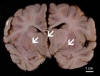

Gross Pathology: The deep gray matter (thalamus and basal ganglia) demonstrate necrosis that involves symmetrical areas which involves mainly the gray matter (large arrows). Similar lesions are also present in the brainstem and cerebellum (small arrows). In all of these areas, there is disintegration of tissue. No hemorrhage is noted. The mammillary bodies are relative unaffected. The area with substantia is extensively necrotic. [Click here to see the gross photos again]